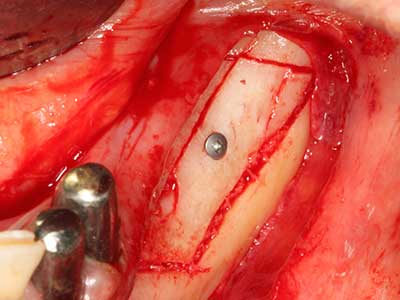

Piezosurgery has additional advantages when harvesting bone blocks. In addition to the high precision with osteotomy described above, the use of the thin saw tips specifically minimizes loss of material. Greater loss of material during harvesting can be expected with the thicker instrument tips, particularly when using Lindemann drills (Lakshmiganthan, Gokulanathan et al. 2012). The basal separation, which is necessary particularly for retromolar block transplants, is simplified by specially designed rectangular saws, with the result that piezosurgery is viewed as a precise, simple and safe procedure for harvesting retromolar bone blocks (Happe 2007) (Fig. 1-12).